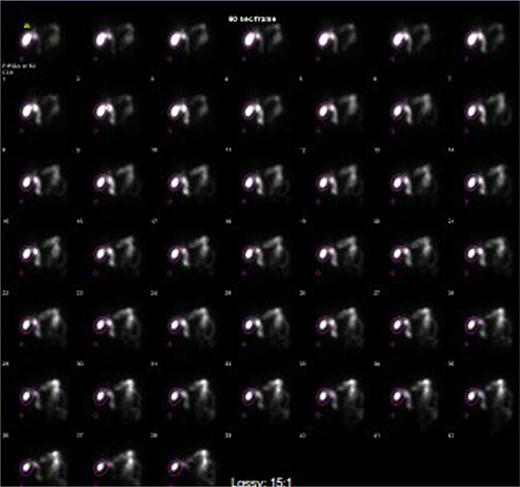

Computed tomography (CT) in the ER showed normal gastric bypass anatomy with moderate colonic stool burden. Negative for biliary pathology. Follow up ultrasound showed cholelithiasis without evidence of acute cholecystitis. A confirmatory HIDA showed normal filling of the gallbladder with rapid clearance into the small bowel and ejection fraction of 62% (Fig. 1).

HIDA scan showing normal gallbladder filling and rapid emptying of nucleotide contrast in the SB following administration of CCK.